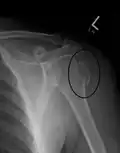

A fracture of the greater tuberosity as seen on AP X ray -

A fracture of the greater tuberosity of the humerus -